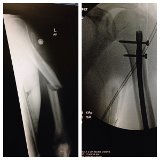

On 12/4/13 exactly one year after my new hip was installed I fell of a ladder falling 12 feet landing on a driveway. My new hip pushed into my pelvis fracturing it and the cup on my new hip twisted sideways due to the impact. My left arm (humerus) was broken in half and I was airlifted to a local hospital.

In a panic and in shock I called Dr. Buly's office and Elaine put everything is action. They worked out a transfer to HSS and organized to have Dr. Helfet to have my pelvis and arm repaired.

We never would have gotten through this without HSS. 8 days in HSS and 3 months later, I was back up on the roof again. I spent the next 6 months working out my new hip, pelvis and arm and I got back in the game.